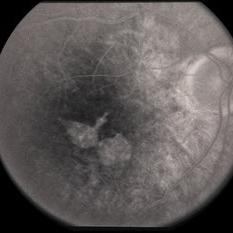

---thumb.jpg/image-square;max$300,300.ImageHandler) Age Related Macular Degeneration - Geographic Atrophy

Age Related Macular Degeneration - Geographic Atrophy

May 3 2013 by Suber S. Huang, MD, MBA, FASRS

Geographic Atrophy.

Imaging device: Retina Diseases Imaging Analysis Reading Center

Condition/keywords: advanced geographic atrophy, atrophic scar, atrophic spot, geographic atrophy, macula lesion, pigment epithelial atrophy